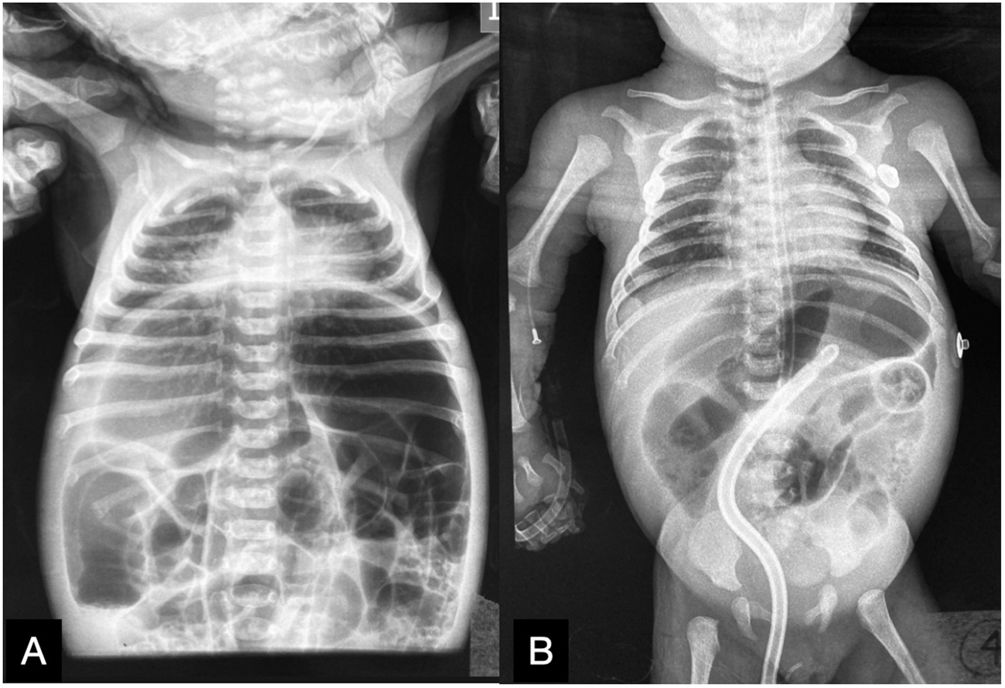

A plain abdominal x-ray was ordered, revealing important intestinal segment dilation (Fig. 1A). An orogastric tube was placed, with abundant output of bile, and a transrectal tube improved the abdominal distension (Fig. 1B). The infant had clinical signs of low cardiac output that responded to dobutamine infusion and presented with oliguria and elevated serum creatinine and blood urea nitrogen. Thyroid panel results were TSH 404 mIU/mL, total T4 0.420ng/dl, T4 0.058ng/dl, total T3 0.195ng/dl, T3 0.321pg/mL, for which treatment with levothyroxine was indicated. Feeding was started with extensively hydrolyzed formula in continuous infusion one week after her admission. Given the clinical presentation consistent with Hirschsprung’s disease, a contrast-enhanced barium enema was ordered that revealed an apparent transition zone in the rectosigmoid colon (Fig. 2), and so rectal irrigations were started. A rectal biopsy was taken, and high-resolution anorectal manometry was performed, documenting the rectoanal inhibitory reflex. Pericardial effusion, anemia, elevated direct bilirubin, and elevated transaminases were detected in the complementary evaluations.